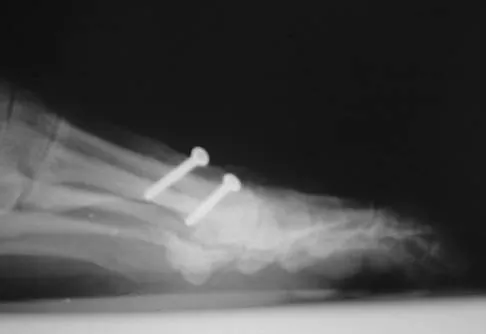

Figure 1 shows the radiograph of an 11-year-old boy who stubbed his great toe while playing soccer barefoot. He is able to walk home despite a small amount of bleeding at the nail fold. Management should consist of

Explanation

Great toe fractures through the physis should be considered open fractures if there is bleeding at the nail fold. Treatment should include irrigation and debridement and appropriate antibiotics. Immobilization with a cast is usually sufficient for treatment of the fracture. Noonan KJ, Saltzman CL, Dietz FR: Open physeal fractures of the distal phalanx of the great toe: A case report. J Bone Joint Surg Am 1994;76:122-125.